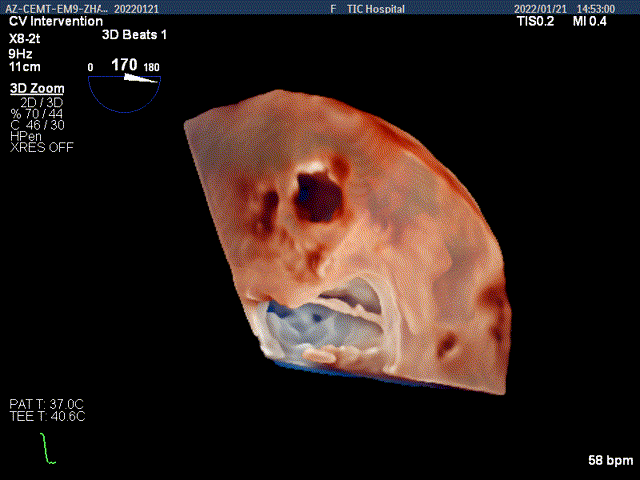

3D MV View:P2区脱垂,宽16.3mm,P3区瓣叶膨隆,与前叶对合不良

Qlab软件勾画估测瓣口面积约:4.42cm²

TEE Bicom view:二尖瓣后叶P2区脱垂,宽16.3mm